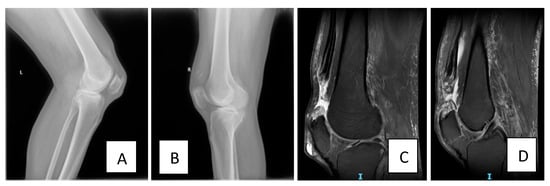

The personal medical and surgical history analysis revealed the patient had type 2 diabetes treated with oral antidiabetic drugs, long-term gout, and hypertriglyceridemia. The patient’s body mass index (BMI) at admission was 26.23, indicating overweight status. The patient denied taking any corticosteroid medication and did not have any prior history of trauma. His general health was stable under standard treatment for the aforementioned conditions. While descending stairs, the patient misstepped and collided with another person, leading to a loss of balance. In an attempt to regain his stability, he rapidly loaded his flexed knees eccentrically—a mechanism that placed excessive tensile stress on the quadriceps tendons while they were contracting to decelerate the fall—ultimately resulting in bilateral tendon rupture. He reported hearing a “popping” sound, immediately followed by intense pain in the suprapatellar region bilaterally and with subsequent inability to stand without assistance. The clinical examination revealed swelling, tenderness, superiorly subluxated patella, suprapatellar depression, pain on the passive knee mobilization bilaterally, inability to perform any active straight leg raise and the extension lag sign positive. The deep tendon reflexes could not be assessed due to the painful palpation of both knees. Patient baseline status was stable; however, a high clinical suspicion of bilateral, simultaneous quadriceps tendon rupture was made during the clinical examination. Bilateral X-ray was performed the same day (Figure 1A,B). Due to limited availability of operating theatres, the patient was transferred to the University Emergency Hospital in Bucharest, Romania. Upon admission, MRI (Figure 1C,D) confirmed the clinical suspicion, revealing complete rupture of the quadriceps tendon at the level of the patellar insertion and quadriceps tendon retraction (Figure 1C,D).

Figure 1. (A) Left knee lateral view on X-ray (preoperative, performed immediately after the incident) showing the low position of the patella. (B) Right knee lateral view on X-ray showing the low position of the patella (preoperative, performed immediately after the incident). (C) Sagittal T2 left knee MRI image (preoperative, performed 1 day after the incident) showing complete rupture of the quadriceps tendon at the level of the patellar insertion with 40 mm retraction. (D) Sagittal T2 right knee MRI image (preoperative, performed 1 day after the incident) showing complete rupture of the quadriceps tendon at the level of the patellar insertion with 24 mm retraction cranially.